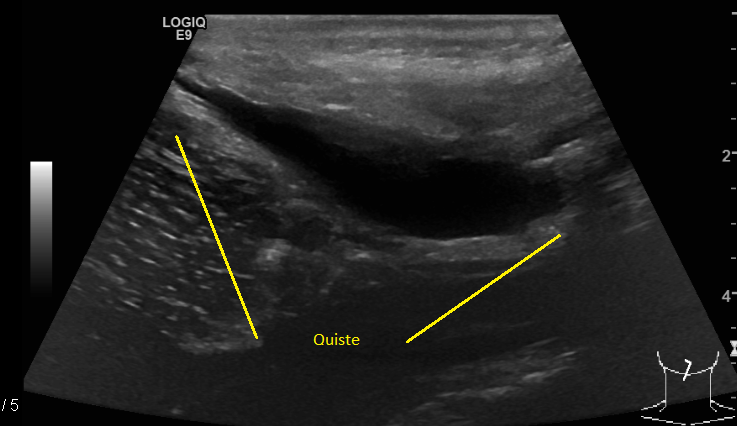

El 23 de enero del 2020 tuve mi segunda revisión de control en el hospital con un ultrasonido. El doctor tuvo los resultados primero y cuando entré a su consultorio estaba muy sonriente y sorprendido de mi recuperación. Yo conocía esa sonrisa. A finales de noviembre el quiste medía 6.8 x 3.5 x 1.6 cm y 20 centímetros cúbicos, y en enero 5.5 x 2.4 x 1 cm y 7.6 centímetros cúbicos.

"Aunque su tamaño no se redujo mucho, sí lo hizo en volumen de centímetros cúbicos: se redujo a más de la mitad de su volumen, lo que quiere decir que seguramente la fístula ya cerró. Ahora es cuestión de esperar a que el cuerpo de manera natural termine de reabsorber el resto del agua como lo ha venido haciendo y, para estar completamente seguros, podrías hacerte otro control a finales de marzo". Esta vez consciente y desde el fondo de mi corazón me sentí muy pero muy feliz: al fin se estaba poniendo fin a esta pesadilla, no más cirugías, no más hospitales, solo cuidados y tiempo. ¡Gracias, gracias, gracias Dios!